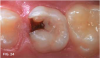

Case 1. A 9-year-old girl had a distal caries lesion of the primary canine tooth and mesial caries of the approximating primary first molar (Figure 1). With no local anesthesia and no discomfort reported by the child, a high-speed diamond bur was used to trim open the contact, exposing the lesions (Figure 2). After the site was air-dried, a flexible interdental pick was used to apply the SDF solution (Figure 3), which was blotted dry with a cotton swab after 60 seconds (Figure 4).

Fig 1. 9-year-old patient with proximal caries lesions of canine and  rst molar.

Fig 1

Fig 2. Surfaces trimmed; caries lesions exposed.

Fig 2